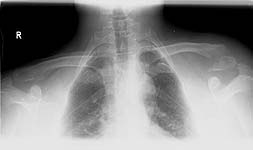

There were some cases of lateral clavicle fractures but right now i have available only images of pure acj cases. The frame is the same as i would assembly for the discussed injury. See attachment.